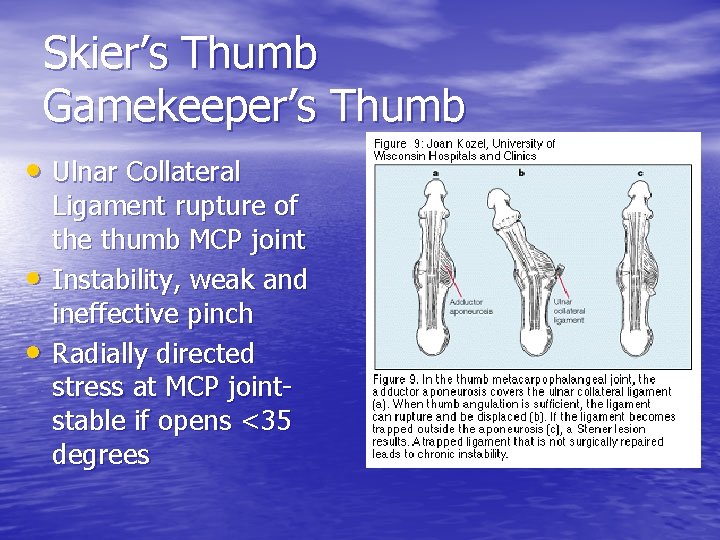

Skier’s Thumb Gamekeeper’s Thumb • Ulnar Collateral • • Ligament rupture of the thumb MCP joint Instability, weak and ineffective pinch Radially directed stress at MCP jointstable if opens <35 degrees